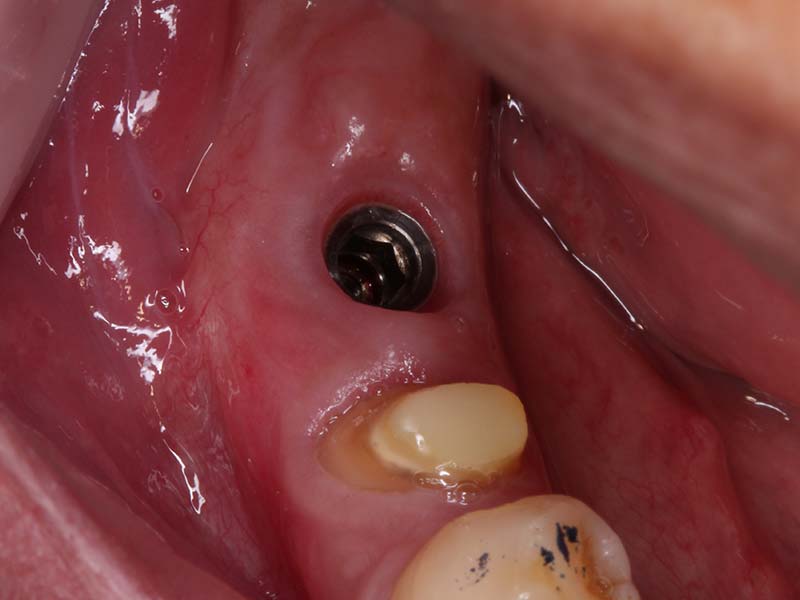

組織增生 首頁 案例分享 組織增生 組織增生 組織增生 缺牙過久,導致組織塌陷 植牙同時合併使用骨粉促進骨頭再生 植牙同時合併使用膠原蛋白,促進牙齦再生 組織穩定後再使用人工皮再增進角化牙齦 Before After 達到理想的組織增生再造